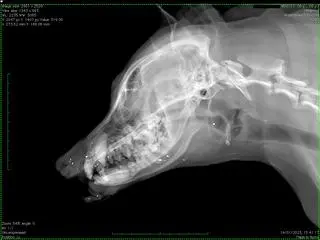

Wendy została postrzelona w pysk

Weterynarz: stan wyglądał dramatycznie

Suczka trafiła do Szpitala Weterynaryjnego Krzemińskiego w Gdańsku. - Stan psa wyglądał bardzo dramatycznie. Miał szarpaną ranę w okolicy pyska, nosa i warg. Jak zrobiliśmy zdjęcie rentgenowskie, to na szczęście okazało się, że kości nie są uszkodzone - przekazała nam Martyna Mohr, weterynarz z lecznicy.